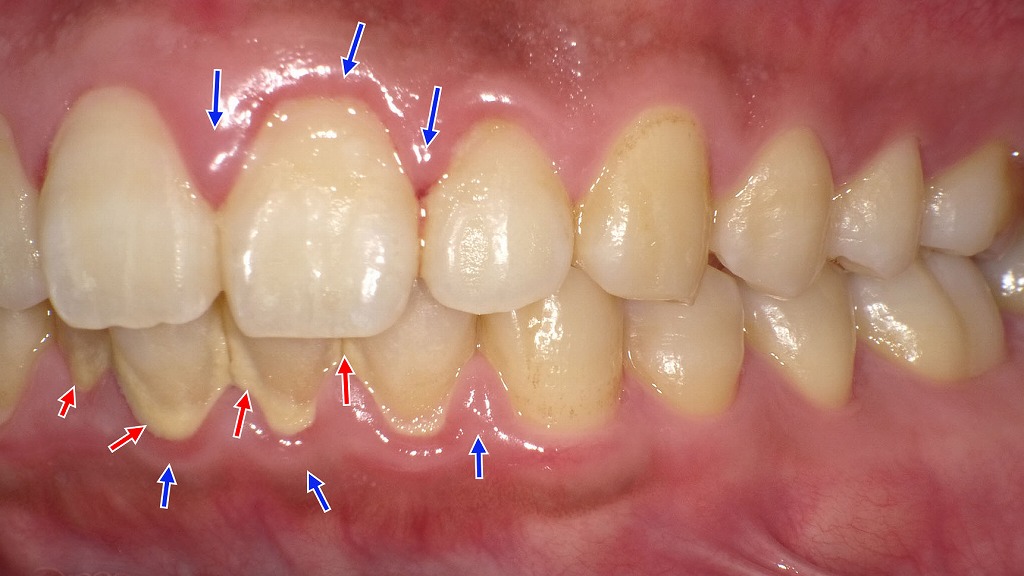

赤矢印は歯の根元や歯間部に付着した歯石を示しています。歯石は細菌の温床となり、歯周病を進行させる大きな原因です。

青矢印は炎症によって腫れている歯ぐきの部分で、歯周病が進行しているサインといえます。

適切な歯周病治療では、歯石除去や歯周ポケット内の清掃を行い、炎症を抑えることで歯を支える組織の回復を目指します。早期に治療を行うことで、歯の動揺や抜歯を回避できる可能性が高まります。